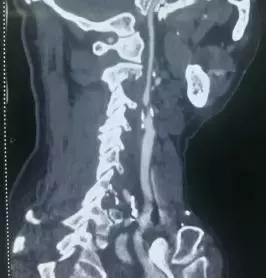

术前DSA检查示左侧颈内动脉重度狭窄